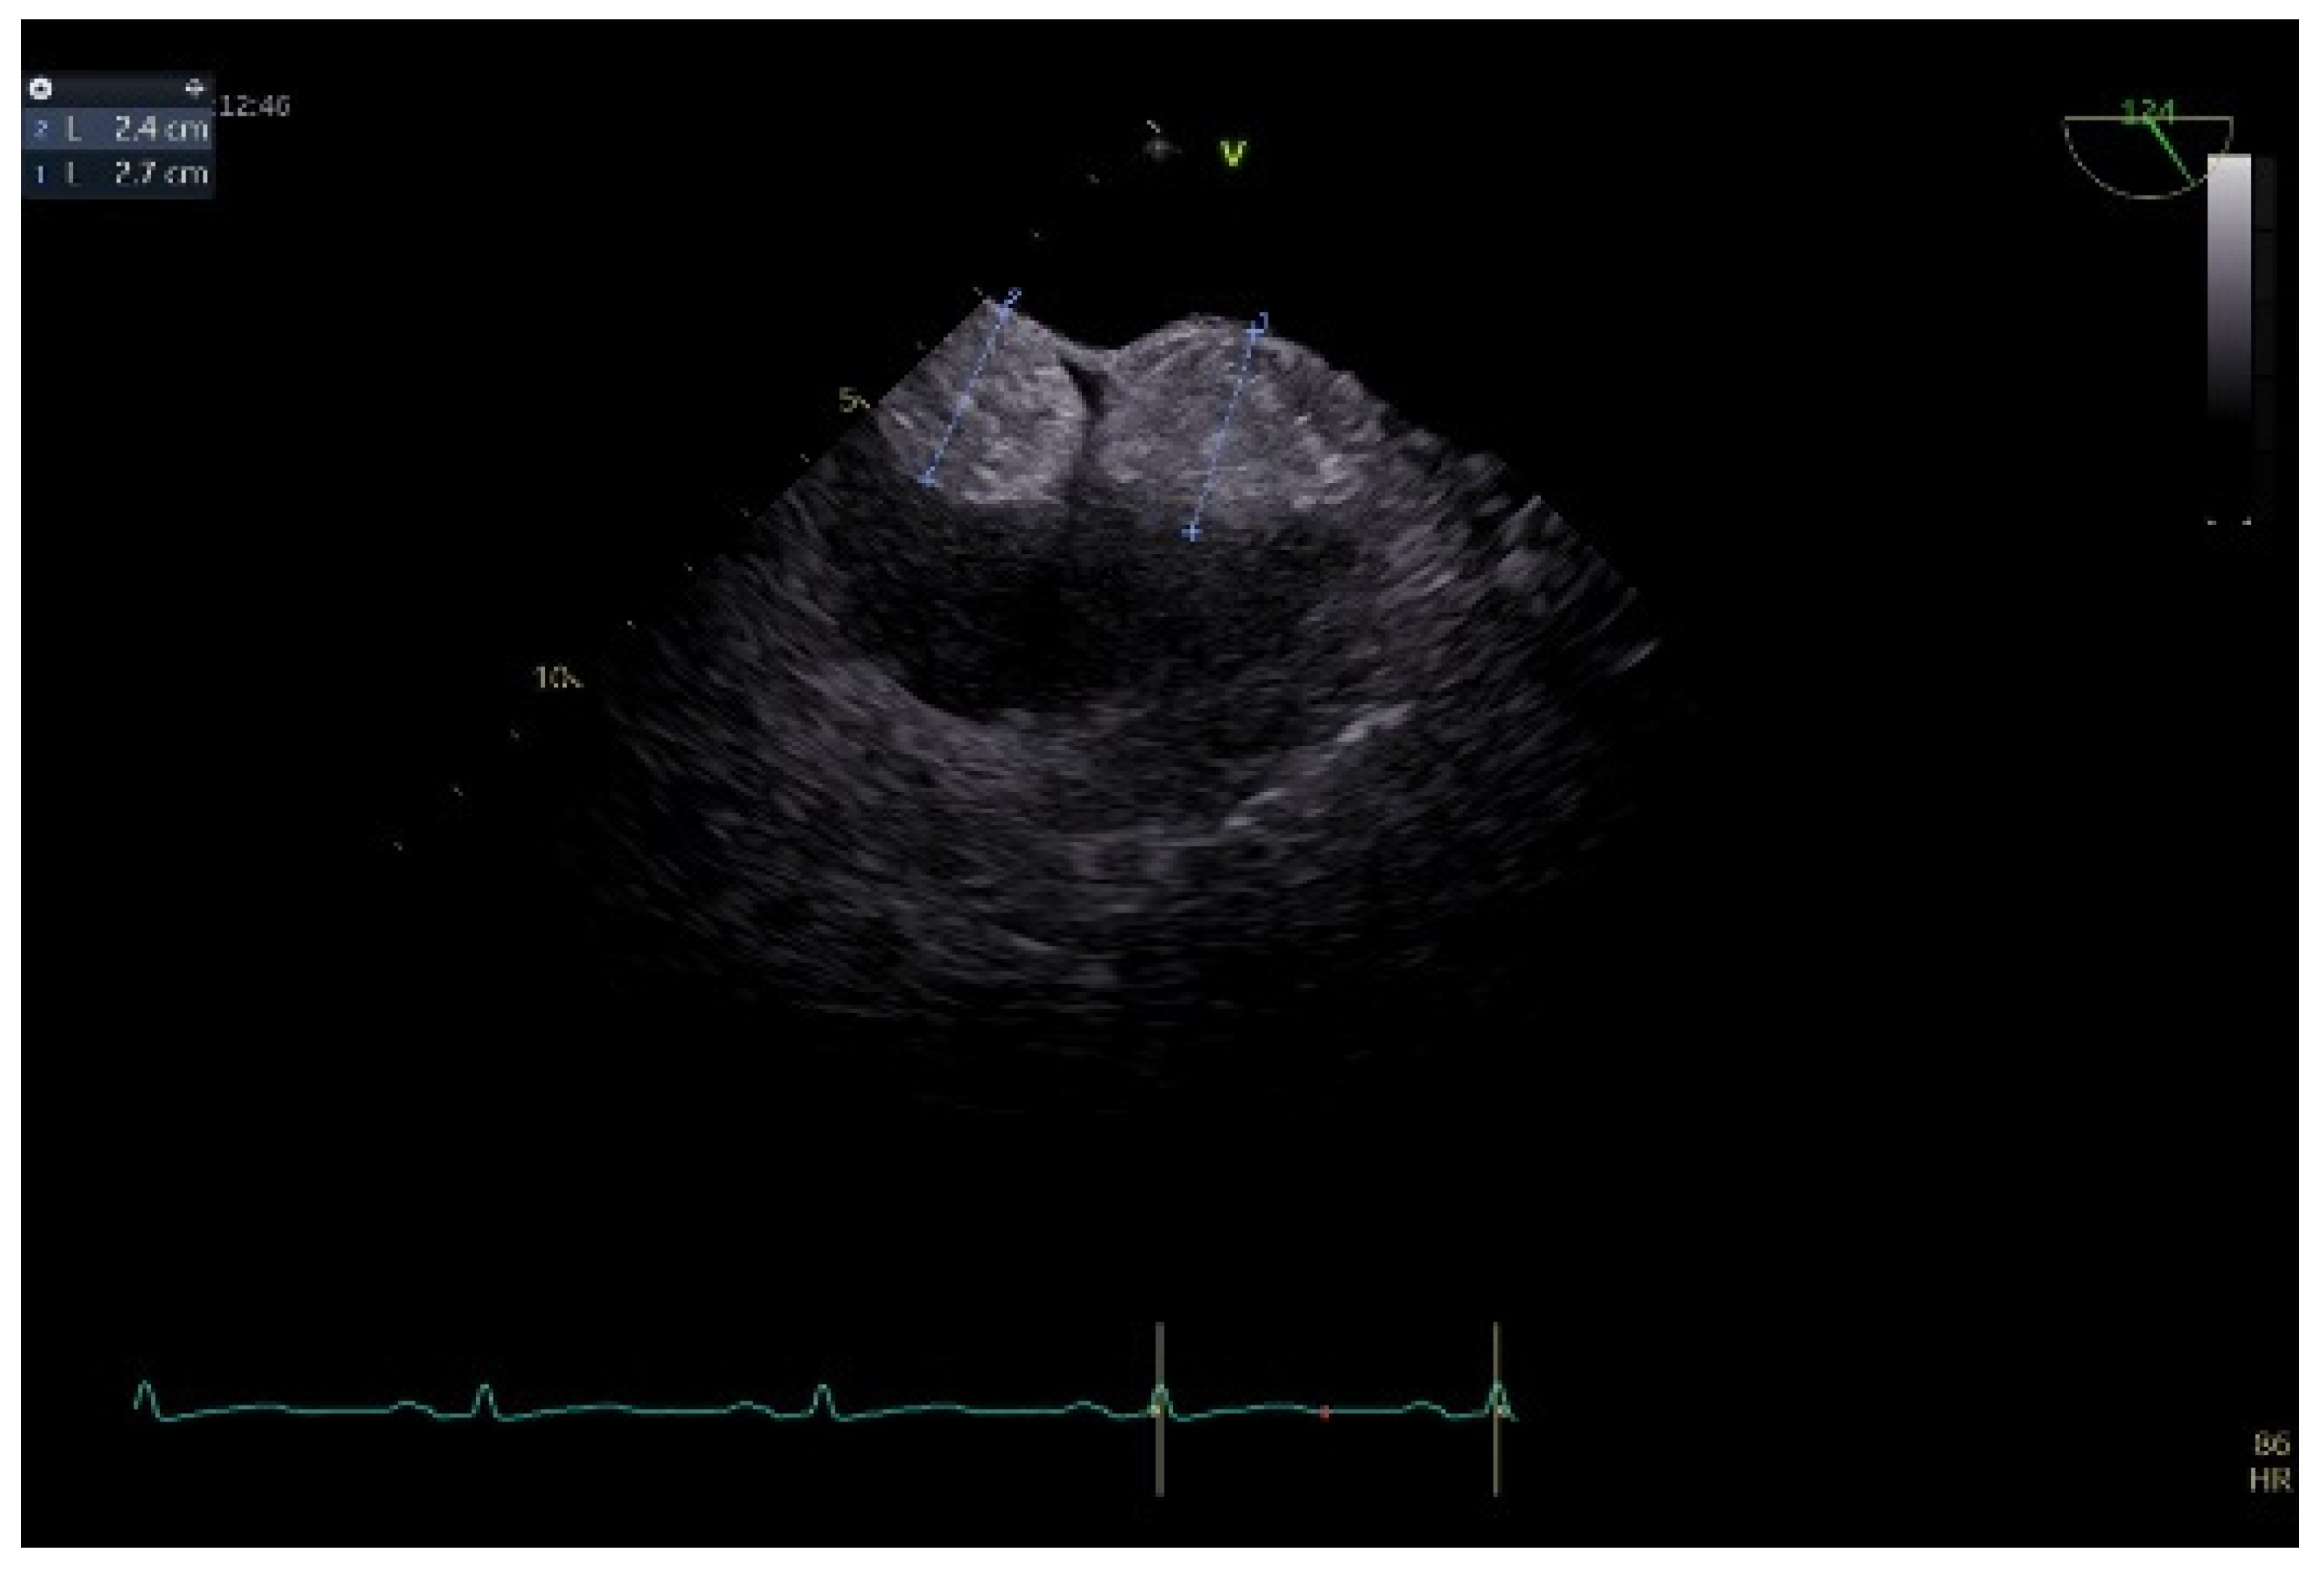

To better describe it, a transesophageal echocardiography was performed. We were surprised to see a second similar so-called mass at the superior pole of the IAS, with the same aspect as described with transthoracic echo. In fact, the IAS was intensely thickened in a diffuse manner except for the fossa ovalis and had the appearance of an “hourglass”, suggesting a possible lipomatous hypertrophy of the interatrial septum. Using both bidimensional (Figure 2) and tridimensional echo (Figure 3), the masses seemed to be encapsulated, homogenous, and attached to the IAS while clearly not being a part of it, aspects that raised some questions in this special patient. There was no color Doppler signal inside the masses, suggesting a lack of vascularization. They lacked any contact and/or continuity with the cardiac valves, an aspect that helped in the differential diagnosis with certain tumors originating on these structures. The right atrial walls were not clearly and entirely viewed. Also, the fact that these masses were not described during previous evaluations was quite unusual. The appearance did not resemble that of a thrombus, since even if the patient had thrombophilia, she was well anticoagulated, and the position and shape of the “masses” did not resemble thrombi. A malignant tumor/metastasis should have been more invasive, irregular, and not respecting the fossa ovalis. The echocardiographic structure of the masses could have resembled a cardiac myxoma though, but possessing two such masses respecting the FO was uncommon. The same situation applies to other possible benign tumors and/or endocarditis. A possible abscess in the context of endocarditis should have also yielded high-inflammation markers. Cardiac amyloidosis was excluded since it did not spare the FO and there were also no other signs of this pathology. Papillary fibroelastoma is usually attached to heart valves, and hemangioma can be found anywhere, most frequently in the LV and RV but also in the RA. Rhabdomyomas are usually found in the ventricular walls and valves, in infants and children. Fibroma is most frequently found in the ventricles, in infants, children, and young adults. Myxoma is normally diagnosed between 30 and 60 years of age, or even earlier if part of Carney syndrome. It can be located anywhere in the heart, but most often within the IAS, pediculated and protruding in the LA. However, a myxoma is a gelatinous non-homogenous mass, due to areas of necrosis and/or hemorrhage, and it sometimes has a villous surface, characteristics that helped exclude this pathology. There are usually multiple malignant tumors which can also be found in any part of the heart. They are irregular masses with an extensive/invasive nature. The most frequent is angiosarcoma which is often located in the RA. Metastatic tumors reach the heart either by direct extension, lymphatic and hematogenous extension, or intracavitary extension through the vena cava and/or pulmonary veins. They are most often secondary disseminations from lung cancer (men) and/or breast cancer (women) [3,7,8,14].

Figure 2.

Bidimensional transesophageal echocardiography, modified bicaval view. Two so-called sessile masses (24–27 mm), at the level of the IAS respecting the fossa ovalis, with the appearance of separate structures.

Figure 3.

Transesophageal echocardiography, tridimensional reconstruction. (a) Four-dimensional zoom acquisition revealing two so-called masses attached to the IAS with the appearance of distinct structures, bulging in the RA (inferior) and imprinting the LA surface of the IAS (superior); (b) 4D zoom acquisition after multislice analysis, confirming the homogenous aspect of the “structures”.